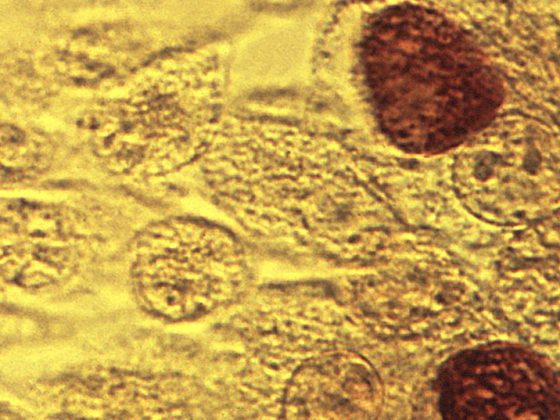

Psoriasisarthritis (PsA) betrifft bis zu ein Drittel der Psoriasispatienten und kann unterschiedliche Gelenk- und Organmanifestationen aufweisen. Dieser Beitrag vermittelt einen kompakten Überblick über klinische Präsentationen, diagnostische Herausforderungen sowie aktuelle therapeutische Strategien gemäß internationalen Leitlinien – inklusive neuer zielgerichteter Therapien. Der Fokus liegt auf Früherkennung, Differenzialdiagnose und individualisiertem Management zur Vermeidung irreversibler Gelenkschäden.